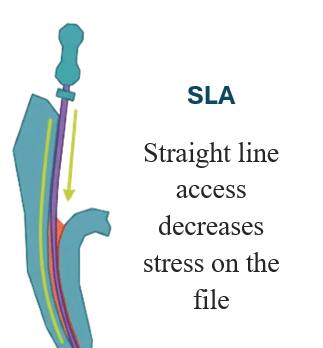

Pre-operative prevention

- Study preoperative radiographs or CBCT.

- Achieve straight-line access.

Step 1 — Improve access

Create straight-line access